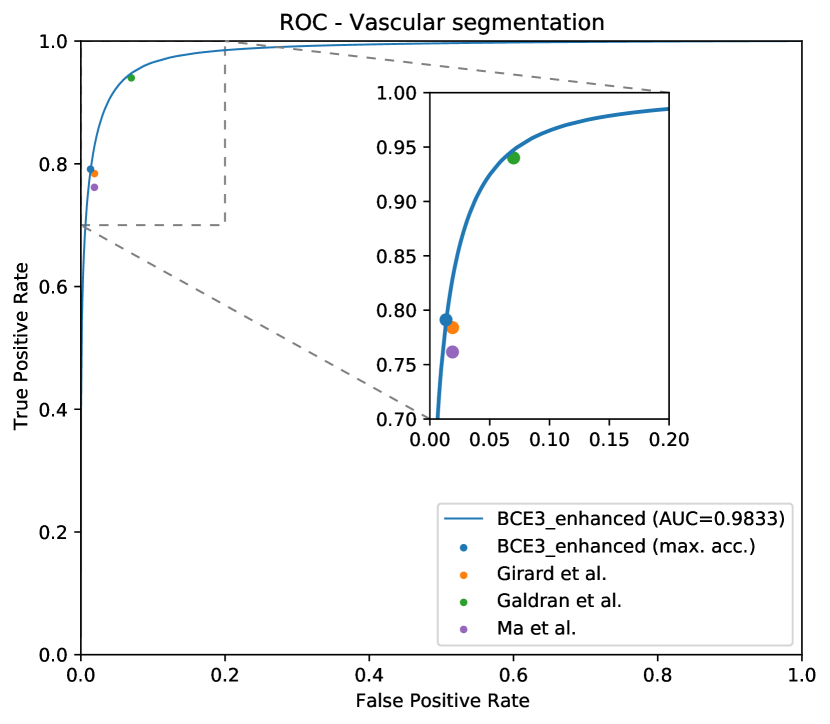

In Figure 8, the mean ROC and PR curves in RITE-test for the networks that were trained using the BCE3 and CE4 losses with and without image preprocessing (“enhanced” and “original”, respectively) are depicted.

As it can be observed in the vasculature segmentation results of Figures 8 and 9 as well as Table 2, the best performance is achieved by the proposed MS approach using the BCE3 loss, either using the enhanced or the original retinography as input, and regardless of the target class. For each structure of interest, i.e. arteries, veins and vessels, both the AUC-ROC and AUC-PR values are higher with the MS approach than with the traditional CE4 one. Furthermore, AUC-PR and AUC-ROC for vessels are significantly higher for the MS approach than for CE4 (), as well as other statistics like AUC-ROC for arteries () and AUC-ROC por veins ().

Regarding the artery/vein discrimination, although the MS alternatives achieve highly positive results (see Table 3), it cannot be affirmed that they perform better than the traditional alternatives. Considering the variability, the A/V classification results of both approaches are not significantly different. However, for the vessel/background discrimination, the situation is different. In this case, consistently with the higher AUC values for vessels segmentation, the MS approach achieves significantly better results () for both Accuracy and AUC-ROC. As can be seen in Table 3, when training with the original images, the sensitivity values of the MS approach are, on average, more than 2.5% higher than those of the traditional approach. Similarly, when training with the enhanced images, the improvement is about 1%. We focus on sensitivity, at a similar level of specificity, due to the positive class that is “vessel”, and the sensitivity measures the proportion of positives that were correctly identified. Specificity and accuracy, although they are also relevant, are much less sensitive in this scenario, since they take into account the background pixels, much more numerous and easier to classify.

Moreover, the methods in the state of the art report the results for a fixed operating point system, with a varying preference for false positives or false negatives among the works. As this complicates the direct comparison between the state-of-the-art results, we complement the results in Tables 4 and 5 with the ROC curves in Figure 15, for the artery/vein classification and the vascular segmentation tasks. In these graphs, we represent the ROC curves for our proposed system (BCE3 loss and enhanced retinographies as input) along with the point representations of the systems in Tables 4 and 5.

As it can be observed in the comparison results, the proposed approach achieves highly competitive results in both the artery/vein classification and the vascular segmentation tasks. In this regard, it is especially relevant that our approach achieves the best performance in the vascular segmentation task among the works aiming at solving both SSCAV tasks, and even a competitive performance with the state-of-the-art specialized methods. This is particularly relevant since, in a real A/V classification scenario, only the detected vessels would be classified into arteries and veins. Regarding the artery/vein classification of the ground truth vessels, however, the achieved results are slightly below the most recent works [40, 41].